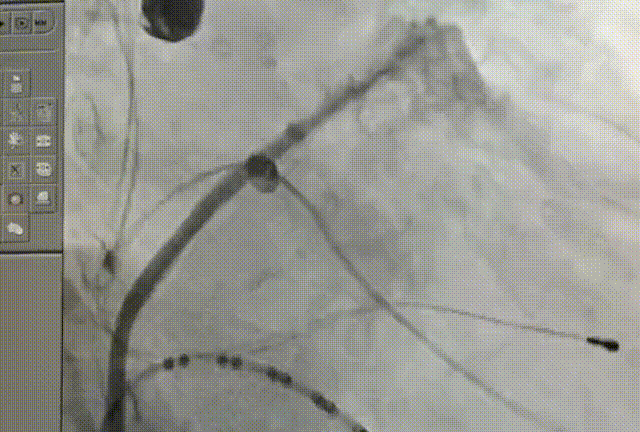

术前CT影像

术前CT结果显示,患者左心耳形态呈鸡翅形,开口呈椭圆形,开口大小约为25mm*20mm, 左心耳深径约20mm。为解决房颤引发脑卒中的后顾之忧,姜小飞教授团队为患者定制了射频消融+左心耳封堵术“一站式”手术解决方案,且由于患者心耳内腔较大,姜小飞教授选择LAmbre™左心耳封堵器进行封堵。

左心耳头位造影

左心耳测量